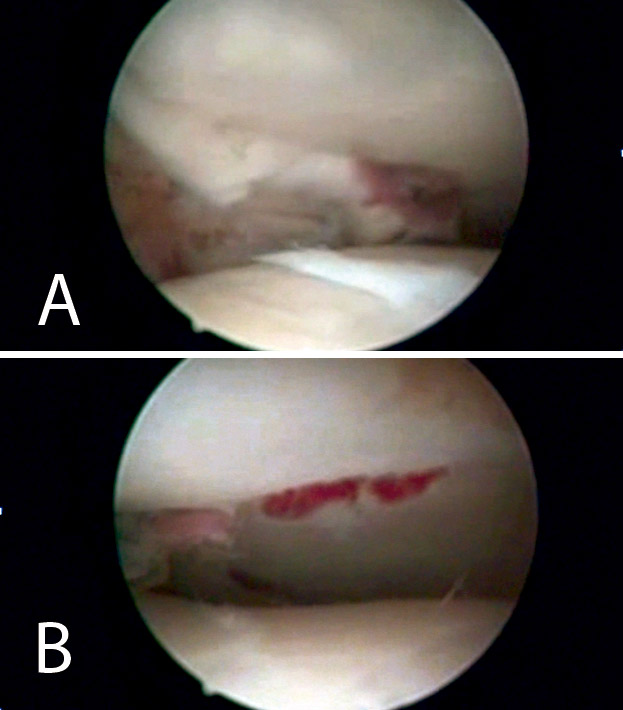

Figura 8. Percusión del fragmento con el impactor, control radioscópico de la posición del impactor e imagen artroscópica del escalón articular antes de la reducción.

Figura 9. Imagen artroscópica de la reducción del fragmento hundido y del trazo articular.